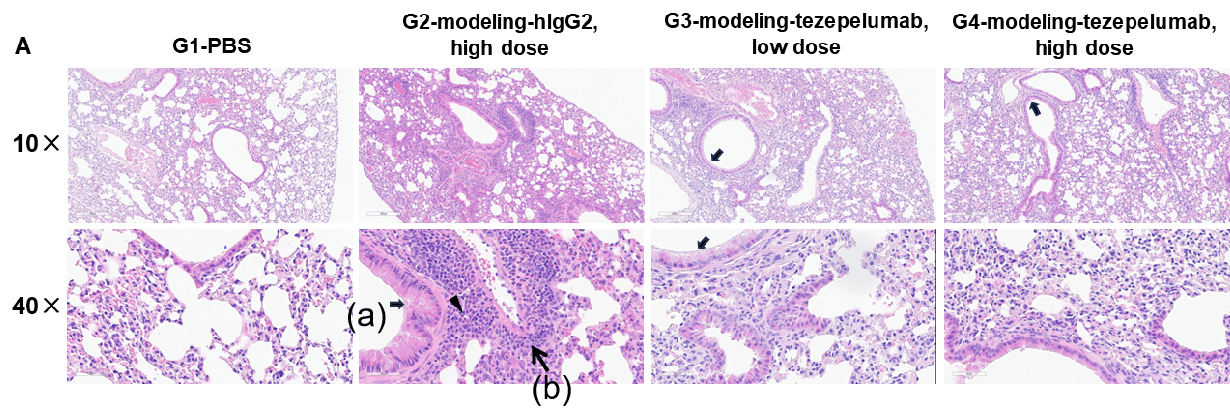

H&E staining and histopathological scoring of lung tissue in TSLP/OVA-induced asthma model of TSLP and TSLP receptor humanized (B-TSLP/TSLPR) mice. Compared to G1 (PBS-treated controls), G2 (TSLP/OVA + isotype) mice exhibited hallmark asthma pathology, including vascular and peribronchial mixed inflammatory cell infiltration (b) and mucus accumulation (a) in bronchi. Tezepelumab treatment in G3 (low dose) and G4 (high dose) reduced airway inflammation and mucus secretion in a dose-dependent manner. Increased inflammatory cell infiltration, mucus production, and eosinophil presence were observed in G2, all of which were attenuated by anti-TSLP therapy, supporting the efficacy of tezepelumab in this allergic asthma model.